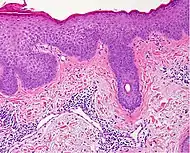

Lichen planus Irregular epidermal hyperplasia with a jagged “sawtooth” appearance, compact hyperkeratosis or orthokeratosis, foci of wedge-shaped hypergranulosis, basilar vacuolar degeneration, slight spongiosis in the spinous layer, and squamatization. The dermal papillae between the elongated rete ridges are frequently dome shaped. Necrotic keratinocytes can be observed in the basal layer of the epidermis and at the dermal-epidermal junction. Eosinophilic remnants of anucleate apoptotic basal cells may also be found in the dermis and are referred to as “colloid or civatte bodies”. Whickham striae are usually seen in the areas of hypergranulosis. Vacuolar degeneration at the basal layer may be noted leading to focal subepidermal clefts (Max Joseph spaces). Squamatization occurs as a result of maturation and flattening of cells in the basal layer. It happens in areas of marked hypergranulosis with prominence of the sawtooth pattern of rete ridges. Wedge-shaped hypergranulosis can occur in the eccrine ducts (acrosyringia) or hair follicles (acrotrichia). In the hypertrophic subtype, the associated hyperkeratosis, parakeratosis, hypergranulosis, papillomatosis, acanthosis, and hyperplasia markedly increased with thicker collagen bundles forming in the dermis. Moreover, the rete ridges are more elongated and rounded as opposed to the typical sawtooth pattern. In atrophic LP, loss of the rete ridges and dermal fibrosis is prominent. In vesiculobullous LP, the disease progression is quicker. Hence, some of the distinctive features such as hyperkeratosis, hypergranulosis, or dense lymphocytic dermal-epidermal infiltrate may not be present. LP lesion may resolve with residual hyperpigmentation caused by a persistent increase in the number of melanophages in the papillary dermis.[9]